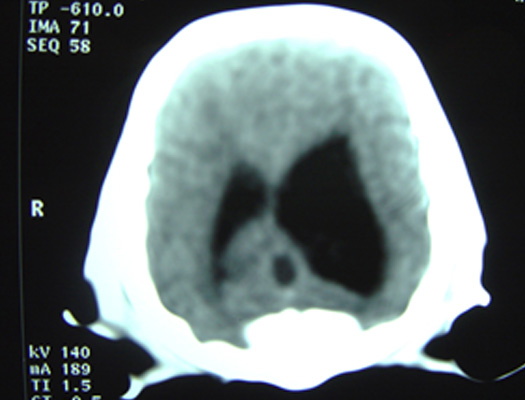

Sarita comienza a presentar signos de incremento de la presión intracraneana (PIC) en forma progresiva. Se le realiza una tomografía cerebral de urgencia observando presencia de hidrocefalia asimétrica marcada y presencia de zonas hiperdensas asimétricas en materia blanca de corteza cerebral.